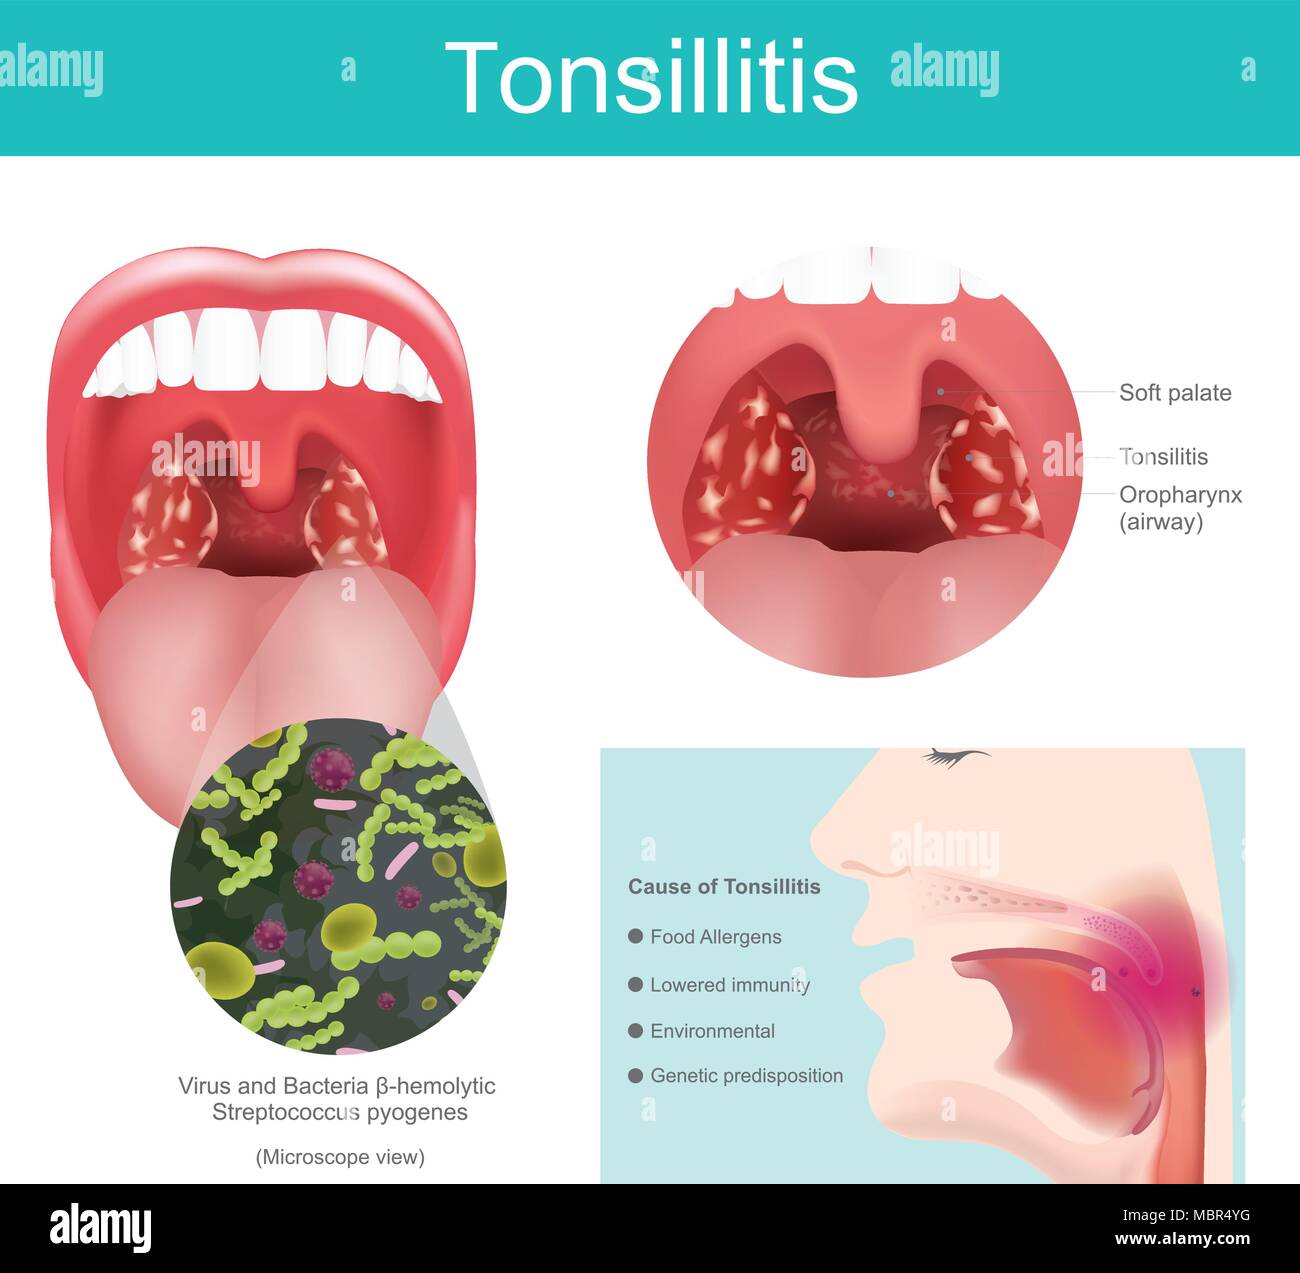

Entzündung der weichen Gewebe im Mund und Schmerzen beim Schlucken auftritt. Durch streptococcus bakterielle Infektionen, einschließlich einige Viren, die es verursacht Stock Vektorhttps://www.alamy.de/image-license-details/?v=1https://www.alamy.de/entzundung-der-weichen-gewebe-im-mund-und-schmerzen-beim-schlucken-auftritt-durch-streptococcus-bakterielle-infektionen-einschliesslich-einige-viren-die-es-verursacht-image179373700.html

Entzündung der weichen Gewebe im Mund und Schmerzen beim Schlucken auftritt. Durch streptococcus bakterielle Infektionen, einschließlich einige Viren, die es verursacht Stock Vektorhttps://www.alamy.de/image-license-details/?v=1https://www.alamy.de/entzundung-der-weichen-gewebe-im-mund-und-schmerzen-beim-schlucken-auftritt-durch-streptococcus-bakterielle-infektionen-einschliesslich-einige-viren-die-es-verursacht-image179373700.htmlRFMBR4YG–Entzündung der weichen Gewebe im Mund und Schmerzen beim Schlucken auftritt. Durch streptococcus bakterielle Infektionen, einschließlich einige Viren, die es verursacht